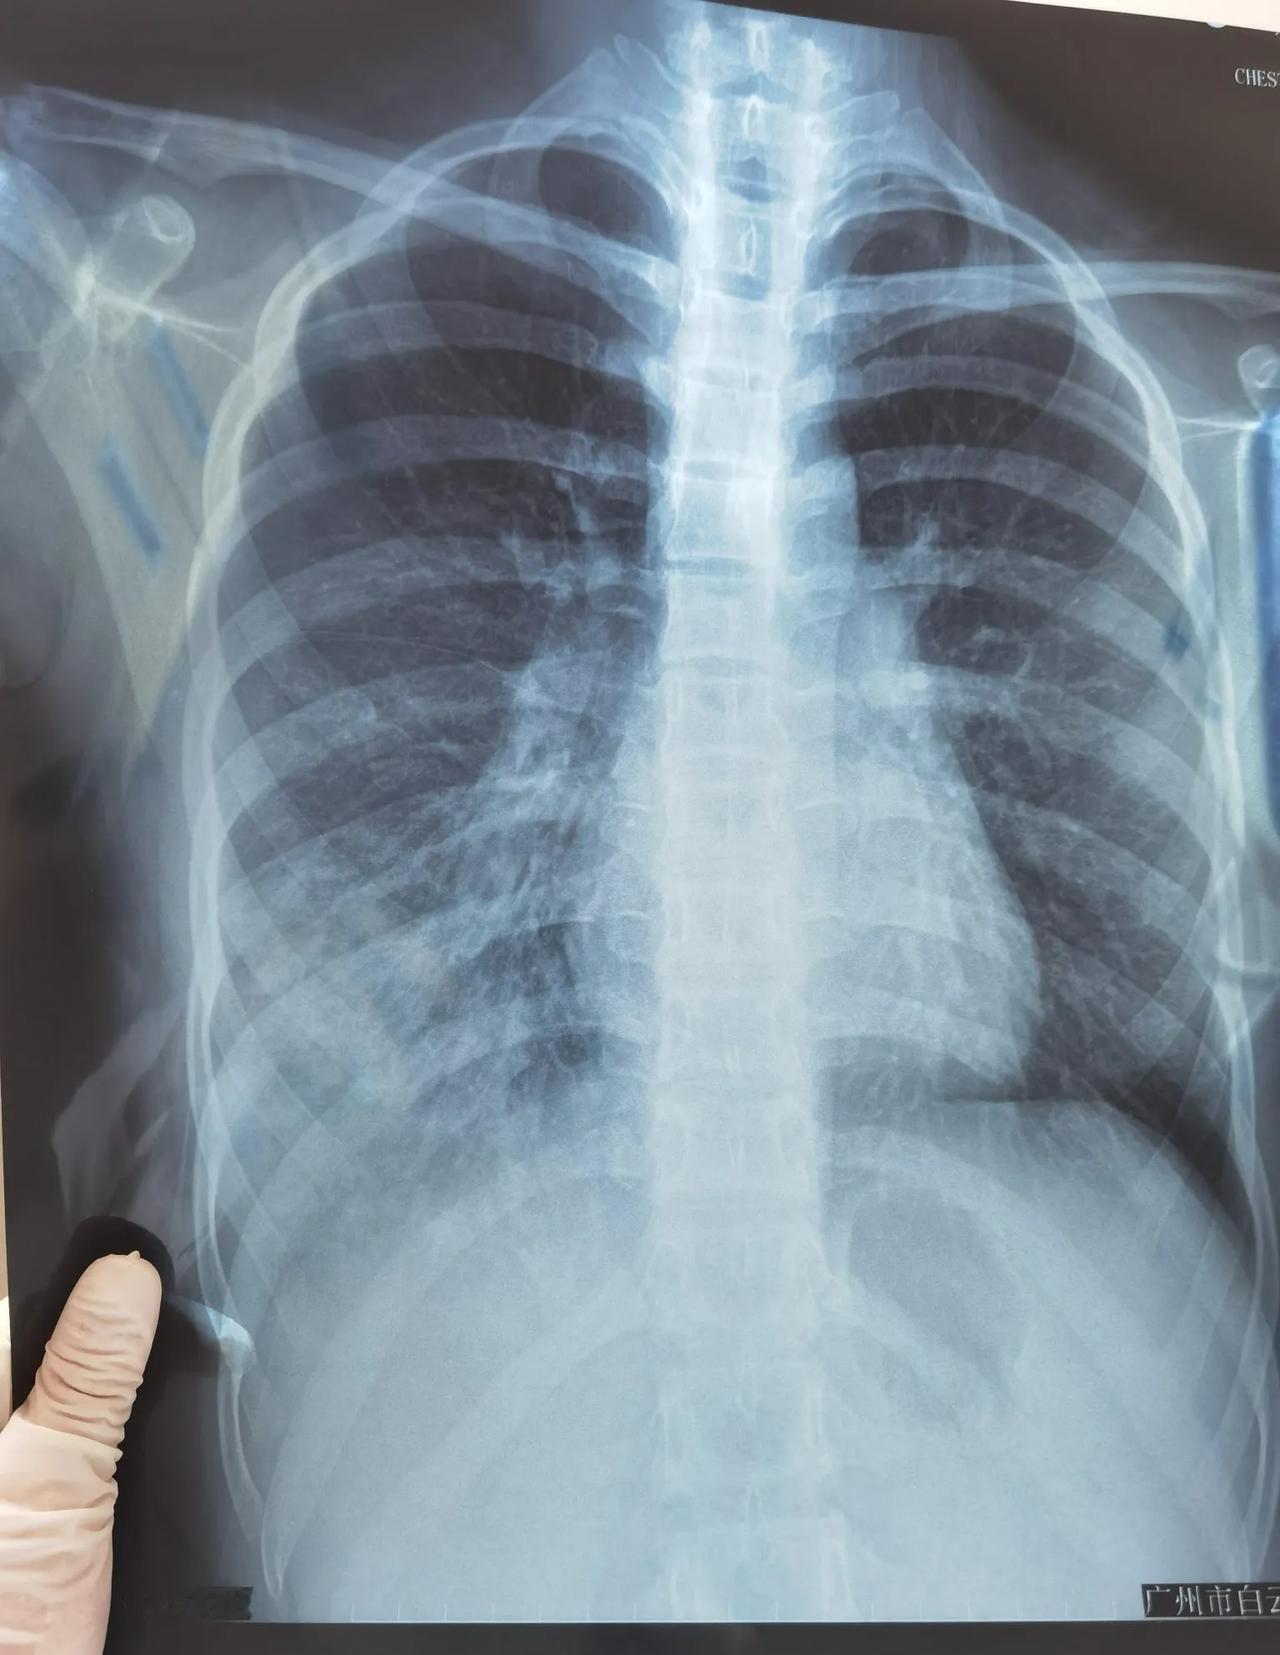

肺炎?肺炎!还是肺炎! 近期呼吸道合胞病毒肆虐,不少孩子又咳又喘,家长稍一疏忽,病情就迅速进展,转眼就成了肺炎。 住院部里,肺炎宝宝们住得满满当当。打针抽血时的痛哭、吸痰护理时的惨叫,夹杂着家长慌乱无措的安慰声,此起彼伏。 一大早,床位就宣告“售罄”,每天都是大进大出,来晚的家庭,只能焦急候床,或者在各大医院间来回奔波,苦不堪言。医生护士们忙的不可开交、汗流浃背,让人担忧的是,不少同事纷纷“中招”,办公室与病房中的咳嗽声交相辉映。病毒环绕之下,谁又能独善其身? 新冠尚未消停,呼吸道合胞病毒已在疯狂肆虐,而手足口病则潜伏暗处,虎视眈眈。 眼下,也只能寄望于,这个暑假,快点到来。